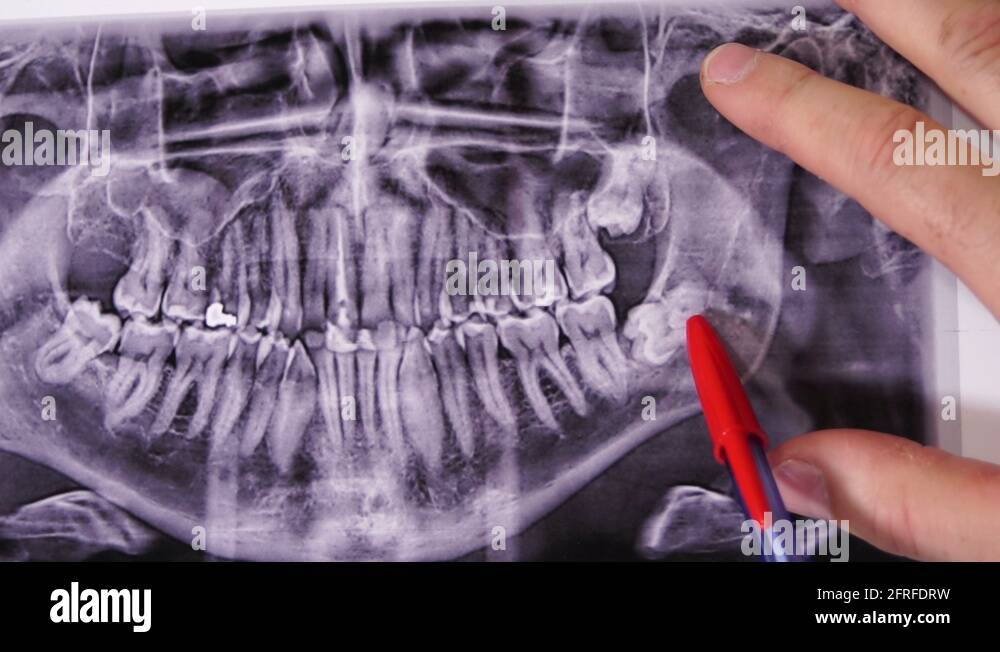

www.shutterstock.comDentistlooking Teeth On X-ray, Wisdom Tooth Stock Image - Image Of

www.shutterstock.comDentistlooking Teeth On X-ray, Wisdom Tooth Stock Image - Image Of

www.dreamstime.comWisdom Teeth X Ray Hi-res Stock Photography And Images - Alamy

www.dreamstime.comWisdom Teeth X Ray Hi-res Stock Photography And Images - Alamy